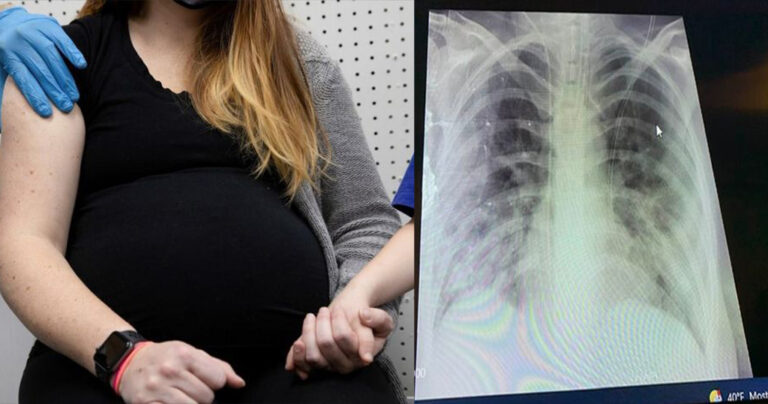

Σοκάρει η ακτινογραφία θώρακα ανεμβολίαστης εγκύου

Ο Καθηγητής Παιδιατρικής του ΑΠΘ, Κοσμάς Σαραφίδης σε ανάρτησή του στο Facebook δημοσίευσε μια ακτινογραφία θώρακα της εγκύου, στην οποία φαίνεται, όπως εξηγεί, ότι λειτουργεί μόνο ο μισός από τον κάθε πνεύμονα.

Στην ανάρτησή του αναφέρει: «Ακτινογραφία θώρακα ανεμβολίαστης εγκύου που διασωληνώθηκε χτες και γέννησε πολύ πρόωρα λόγω της βαρύτητας της κατάστασης της. Μόνο ο μισός από τον κάθε πνεύμονα της λειτουργεί. Άγνωστη η πρόγνωση της μητέρας. Και ένα νεογνό που θα μπορούσε να γεννηθεί στην ώρα του, τελειόμηνο, και να αποφύγει όλους τους κινδύνους της προωρότητας.

Αυτό που γράφεται σε ανάλογες περιπτώσεις, ότι δηλαδή το μωρό σώθηκε, είναι τελείως ανακριβές. Μήνες εντατικής νοσηλείας για να επιβιώσει και μόνο! Και με νευροεξέλιξη απρόβλεπτη σε μεγάλο βαθμό! Κρίμα, κρίμα! Τα σχόλια είναι περιττά!».